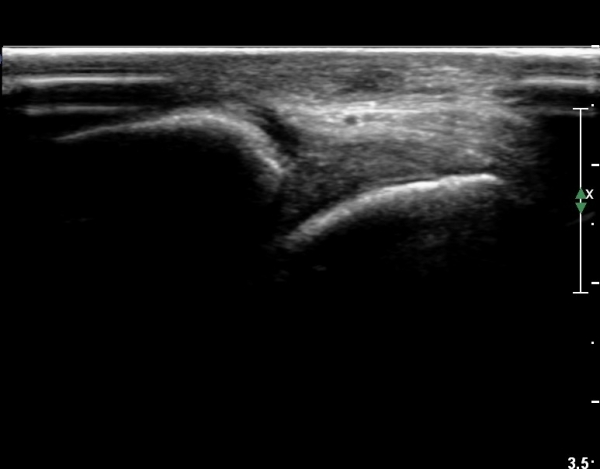

Àü°ÅºñÀδë Á¾´Ü¸é°Ë»ç¿¡¼­ ºñ°ñ ºÎÂøºÎ Àü°ÅºñÀδëÀÇ Àú¿¡ÄÚºÎÁ¾°ú ÀÎ´ë ¸»´ÜºÎ¿¡¼­

ºñ°ñÀÇ °ß¿­°ñÀýÀÌ °üÂûµÈ´Ù(»çÁø 3, 4).